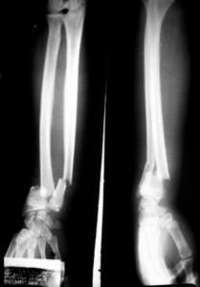

Ampliar la imagen Fracturas de f�r, v�ebras y mu�, las m�frecuentes FOTO Fabrizio Le�

A esta cifra habría que agregar los gastos para el tratamiento de las fracturas de vértebra y muñeca, las cuales son todavía más frecuentes. El especialista participó en una conferencia de prensa en la que el laboratorio Merck Sharp and Dohme (MSD) anunció la realización de una campaña de detección de osteoporosis en el país.

También comentó que lo más común es la fractura de vértebras y, sin embargo, es de la que existen menos diagnósticos. Se presenta cuando las vértebras están comprimidas, hay pérdida de estatura y encorvamiento de la espalda. La postura inadecuada ocasiona un abdomen protuberante y trastornos respiratorios y digestivos.